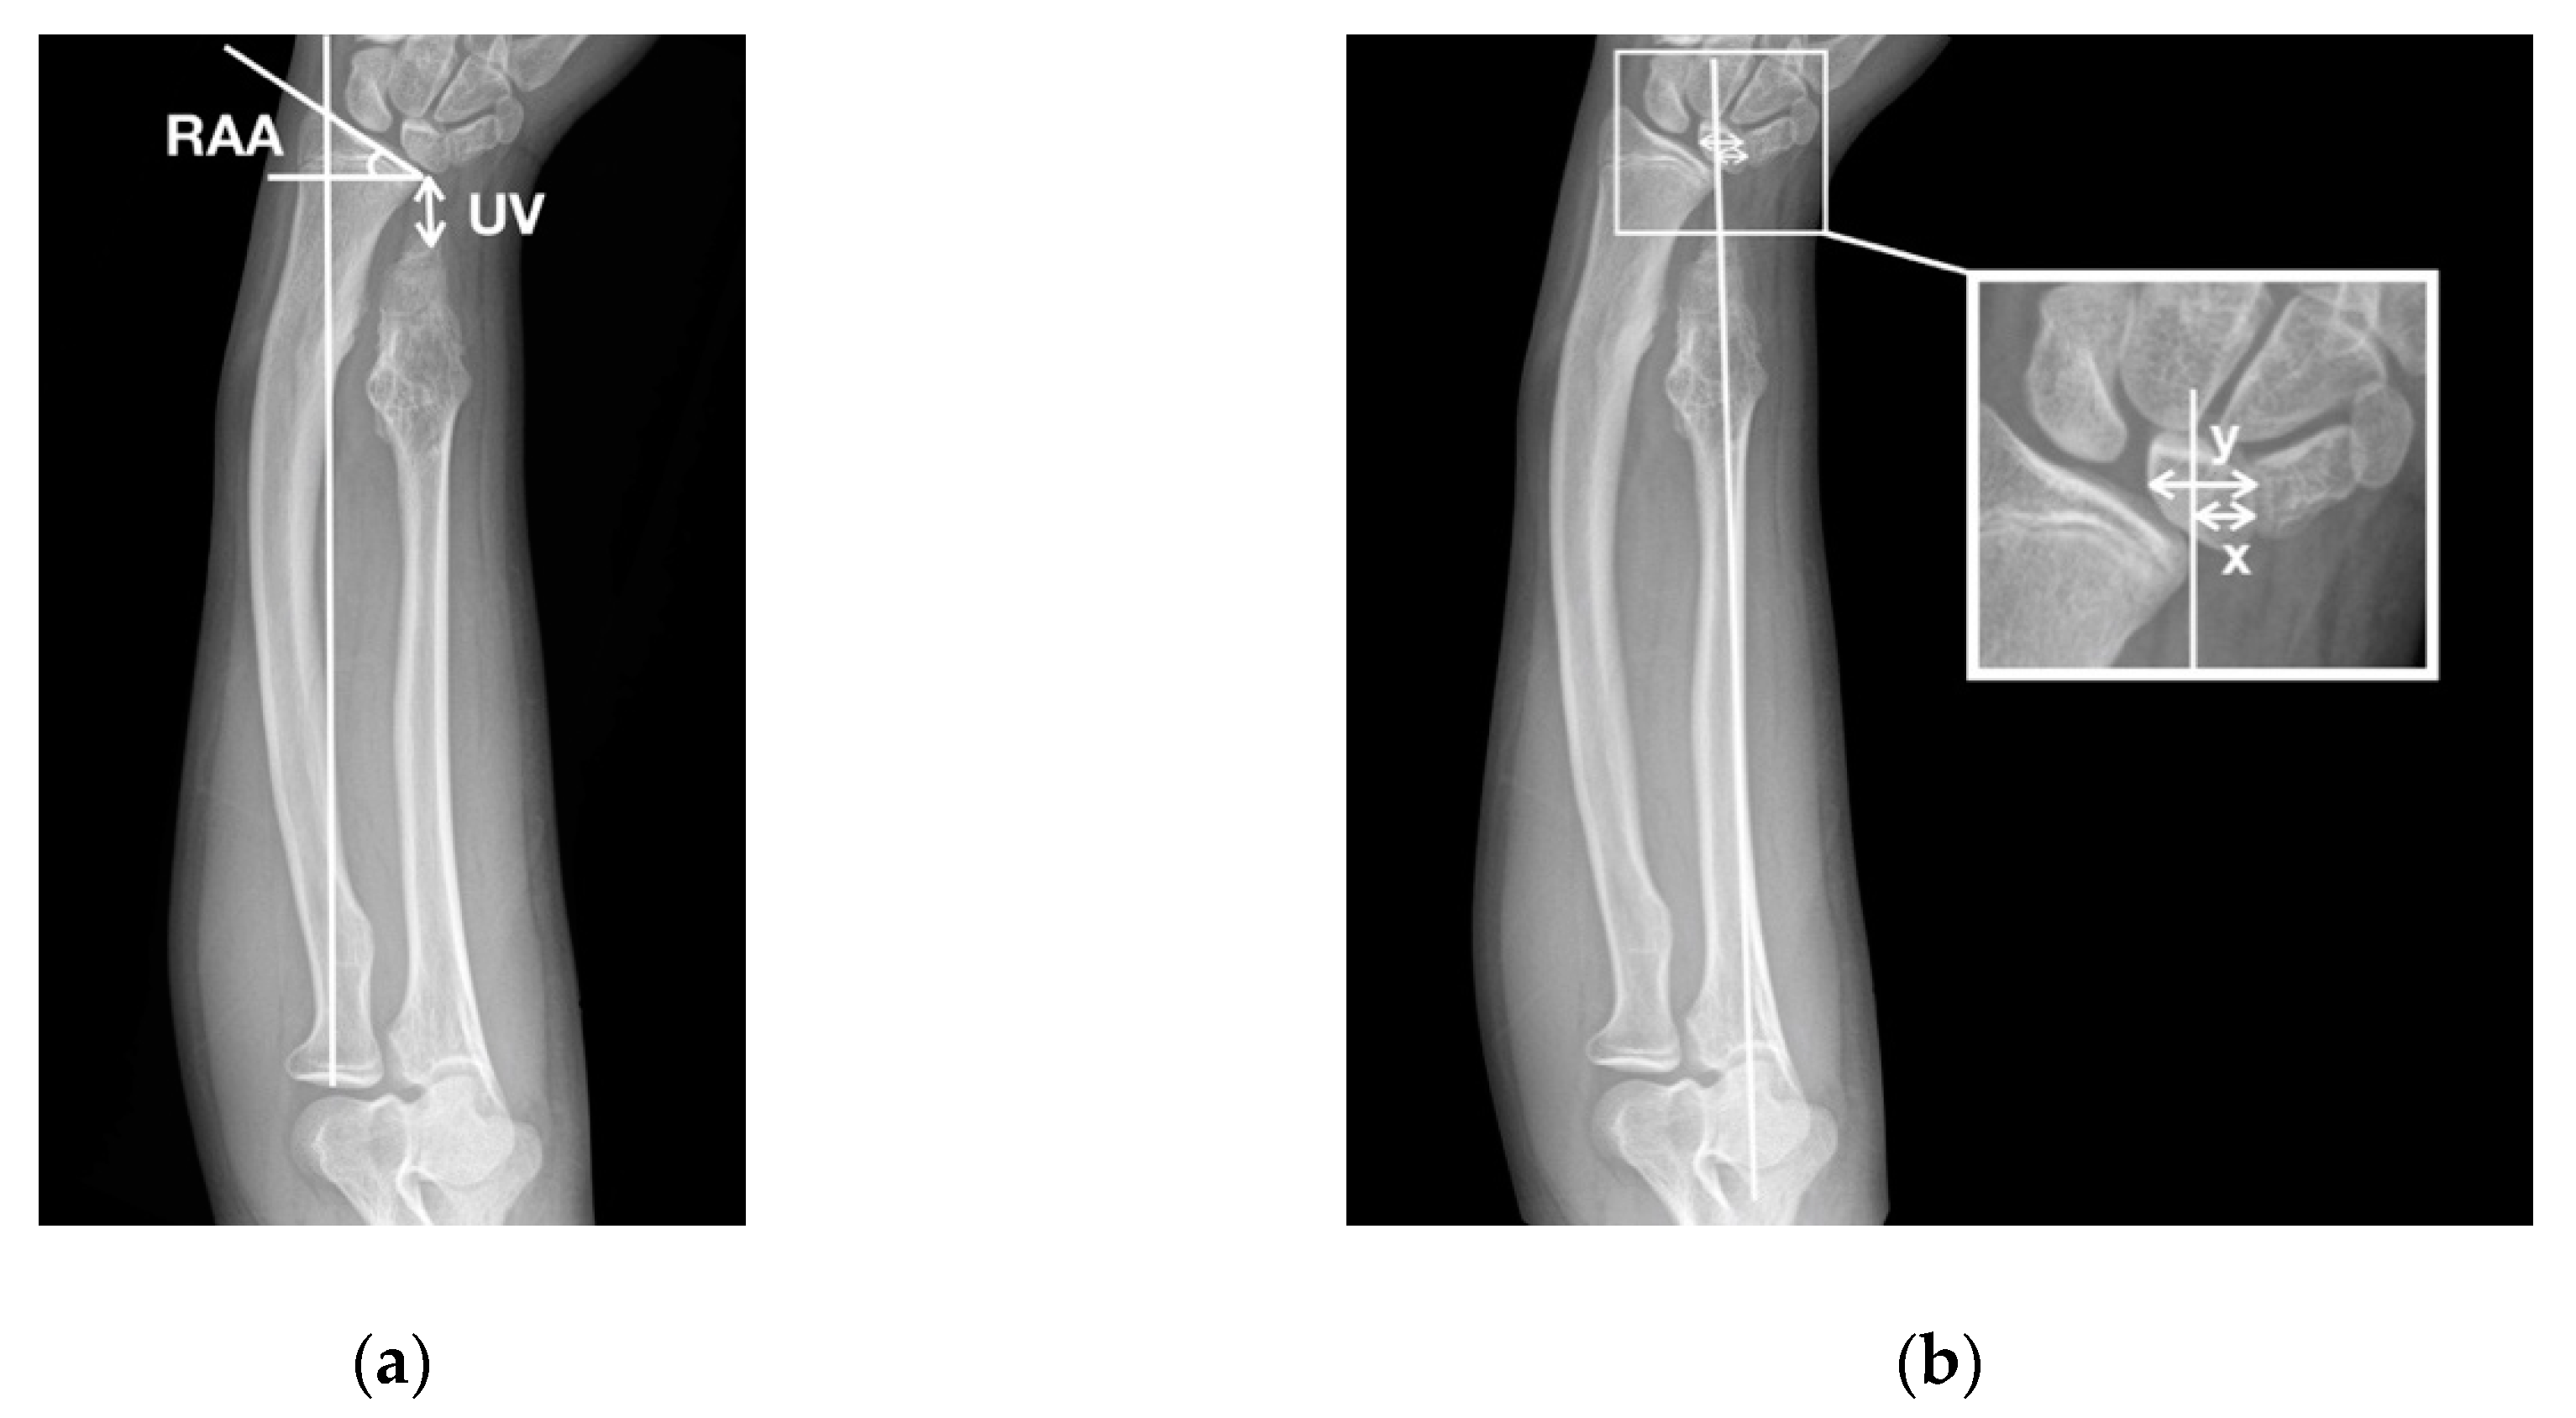

| UV (mm) | |||

| Preoperative | −16.8 ± 2.9 | −14.5 ± 2.4 | 0.11 |

| Follow-up | −0.2 ± 3.2 | −4.6 ± 7.0 | 0.32 |

| RAA (°) | |||

| Preoperative | 35.8 ± 5.2 | 38.8 ± 2.5 | 0.44 |

| Follow-up | 22.9 ± 4.7 | 31.2 ± 7.7 | 0.07 |